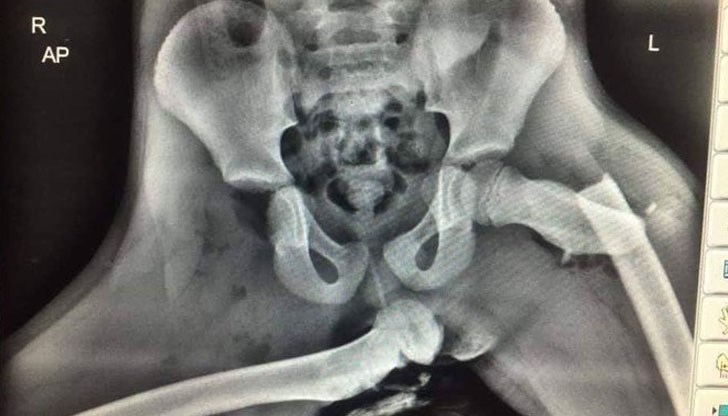

Рентгеновата снимка показва последиците за младо момиче, попаднало в катастрофа, докато държало краката си опрени на арматурното табло. Дори неспециалист може да види, че едната бедрена кост е счупена, а другата се е извадила от гнездото на таза, вероятно разкъсвайки меките тъкани в тази толкова деликатна област.